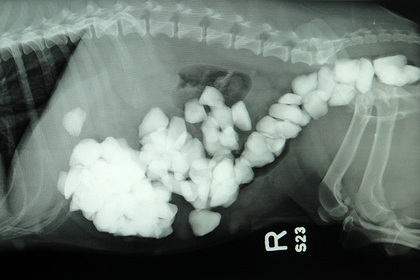

圖自臺媒中新網8月26日電據臺灣媒體報道,英國蘭開夏郡一頭杰克羅素梗犬,平常都在主人家撲滿碎石子的后院玩,日前主人發現小狗精神很差、食欲不振,帶它去看獸醫。

獸醫判斷小狗腹內有異物,照了X光后大吃一驚,原來小狗的腸道內已經塞滿了大大小小的石頭,經過緊急手術將石頭取出,竟有80多顆。

獸醫表示,如果不馬上處理,小狗的腸道可能破裂。現在小狗已經恢復健康。